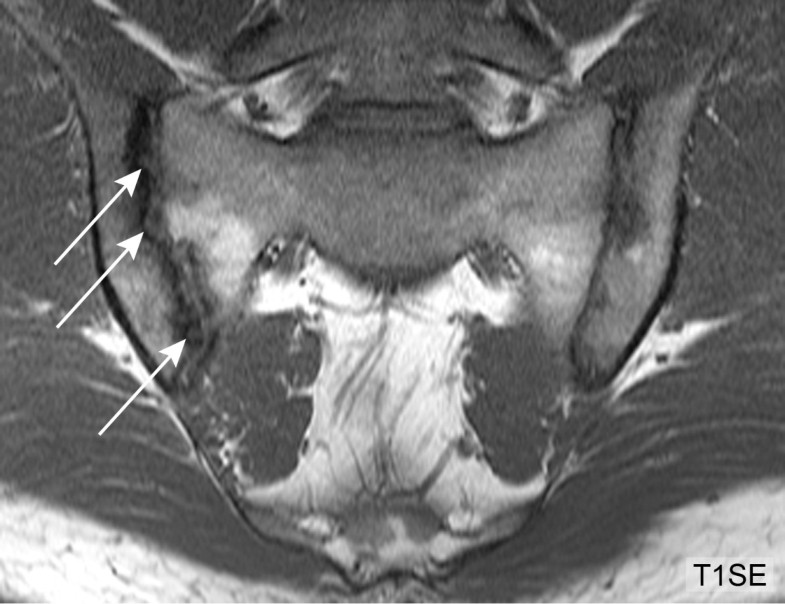

MRI for diagnosis of axial spondyloarthritis major From rmdopen.bmj.com